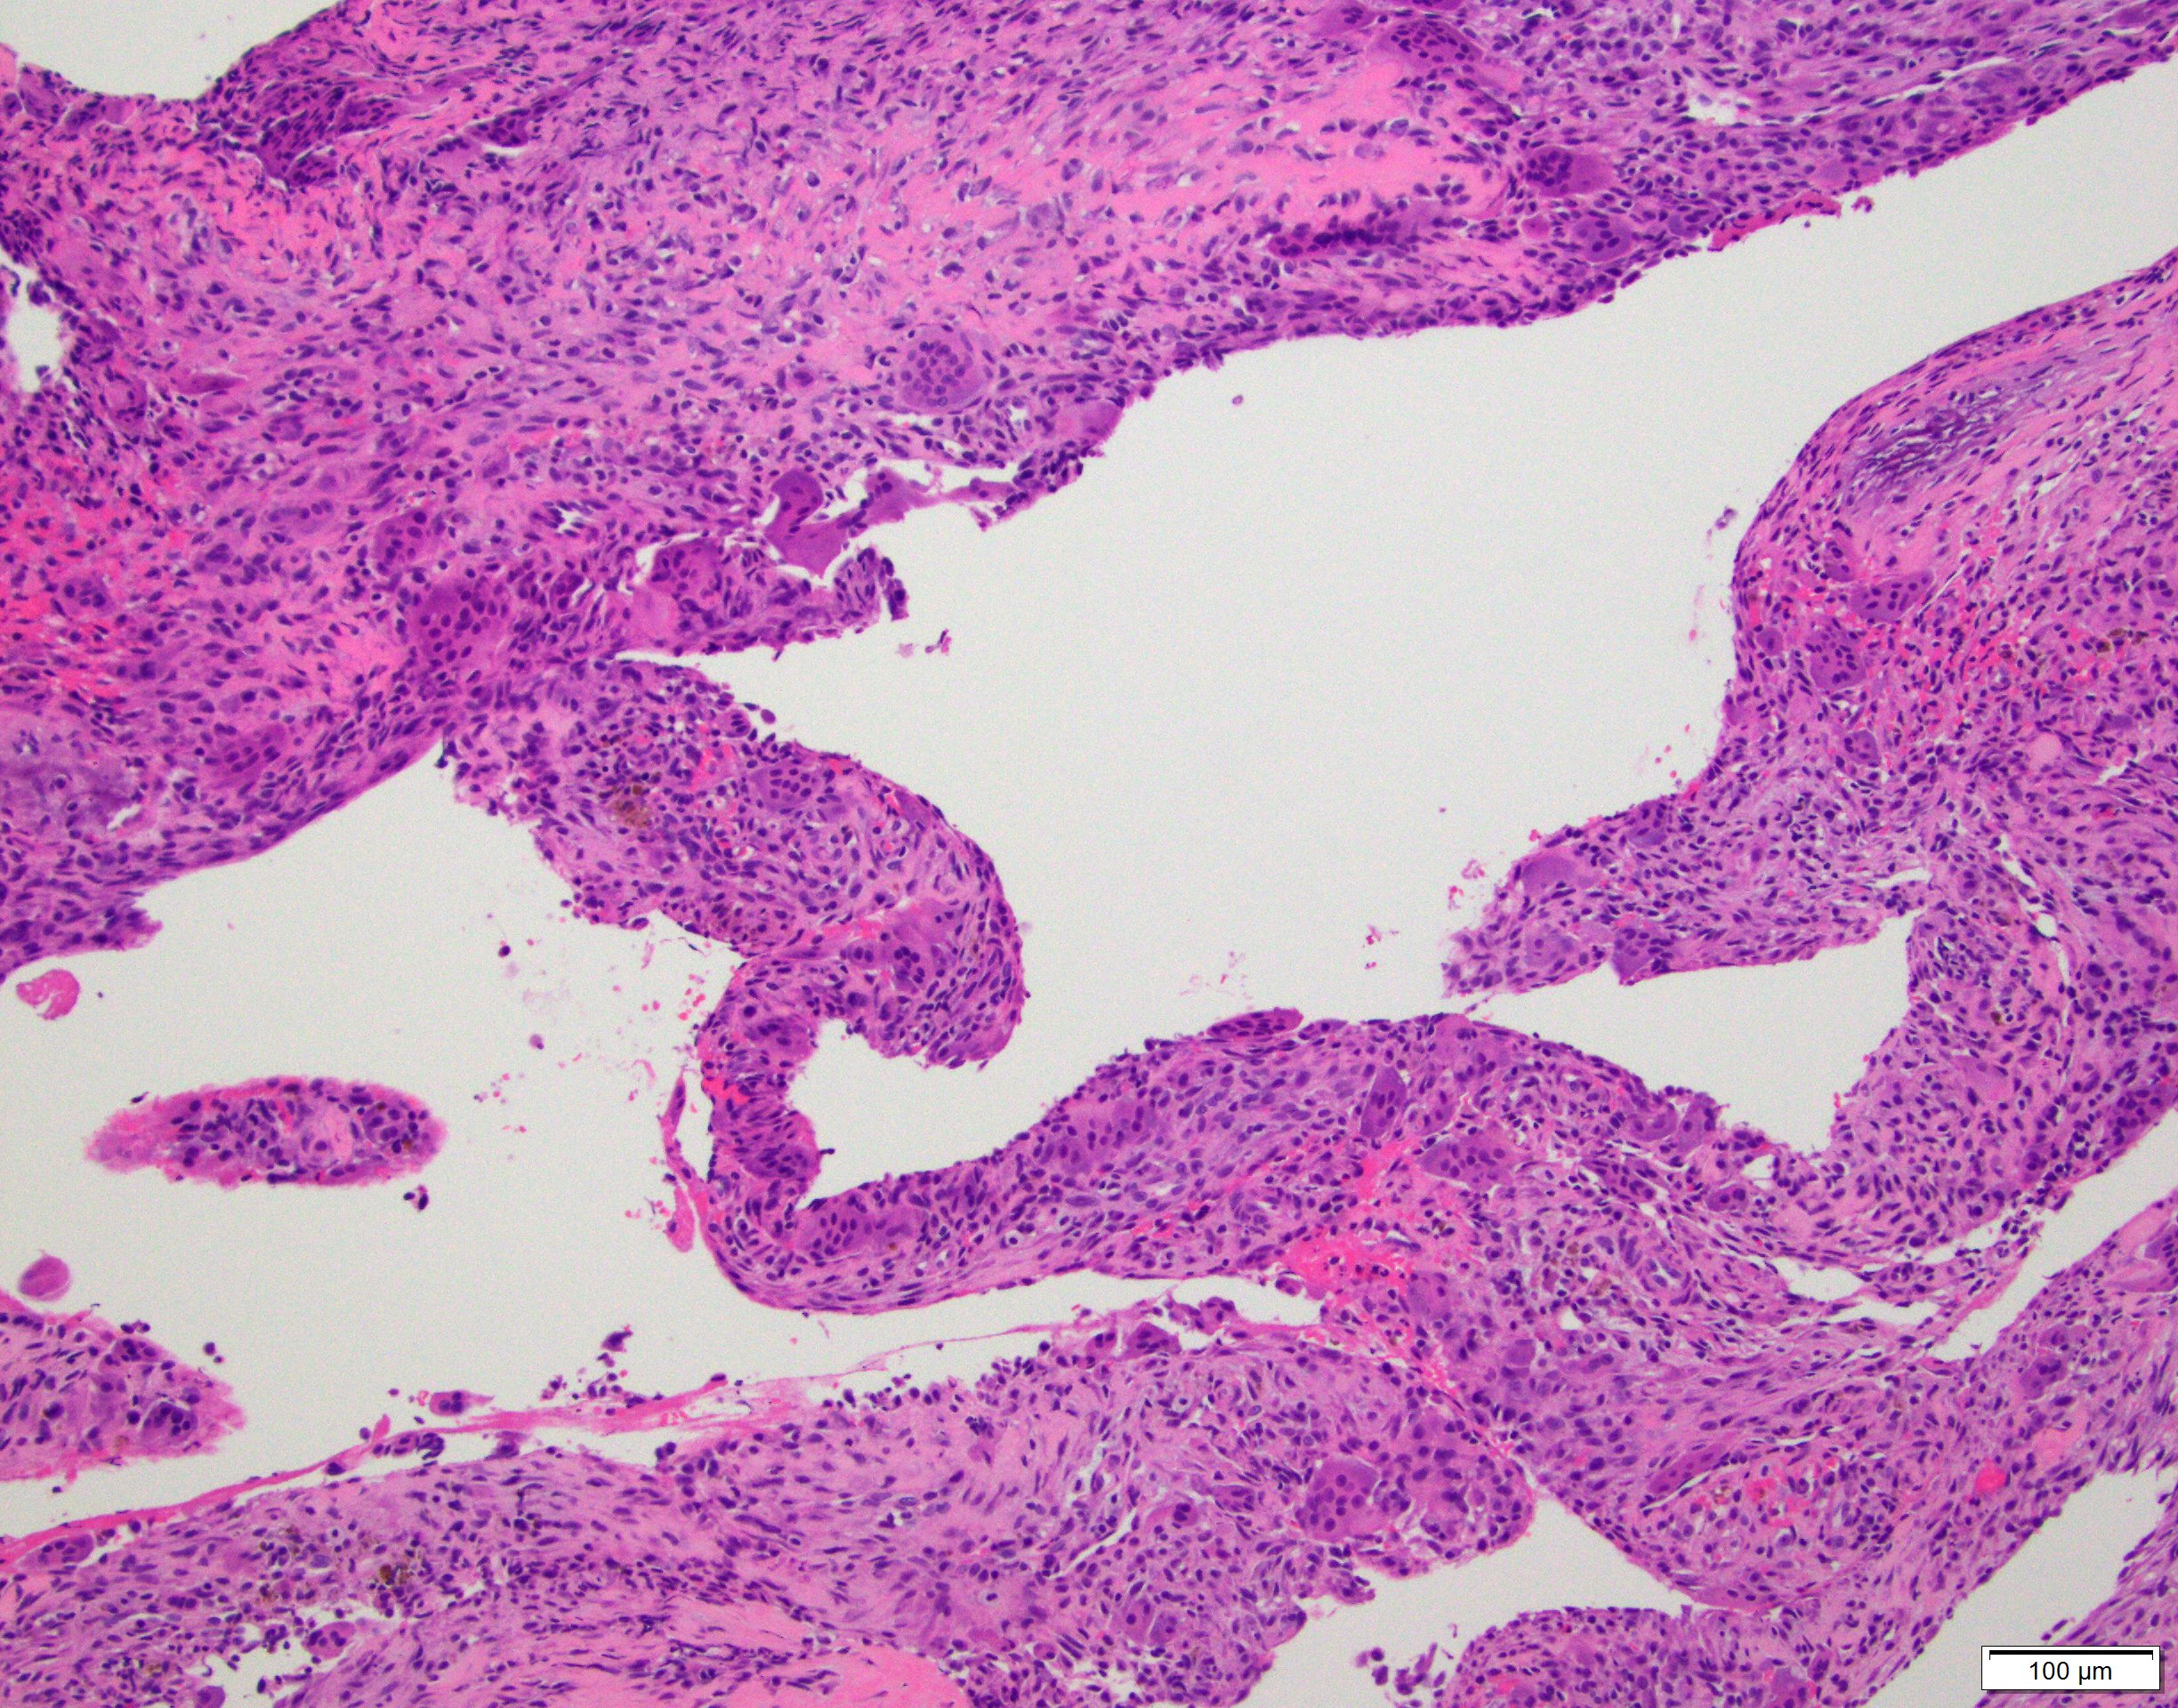

- Multiloculated cystic lesion

- Blood filled cystic spaces separated by cellular septa containing fibroblasts, giant cells and woven bone

- Calcified, basophilic material (blue reticulated chondroid-like material)

- Necrosis not common but mitotic activity is easily identified

- No cytologic atypia (Am J Clin Pathol 2015;143:823)

- Numerous giant cells in connective tissue that line large sinusoidal spaces

Microscopic (histologic) images

Contributed by Elham Nasri, M.D. and Kelly Magliocca, D.D.S., M.P.H.

A. Aneurysmal bone cyst. The H&E shows cystic spaces with stromal giant cells. Rearrangement of USP6 gene confirms the diagnosis in the above clinical and radiographic context.